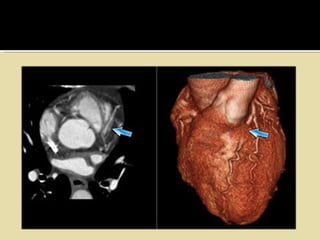

 Bridging of coronary arteries:

▪ anomalous pathway of the epicardial arteries

▪ intramural course.

▪ On contraction of the myocardium, the artery gets occluded causing

ischaemia.

• #26 ALCAPA On the left images of a patient with an anomalous origin of the LCA from the pulmonary artery, also known as ALCAPA. ALCAPA results in the left ventricular myocardium being perfused by relatively desaturated blood under low pressure, leading to myocardial ischemia. ALCAPA is a rare, congenital cardiac anomaly accounting for approximately 0.25-0.5% of all congenital heart diseases.  Approximately 85% of patients present with clinical symptoms of CHF within the first 1-2 months of life.

• #27 Myocardial bridging Myocardial bridging is most commonly observed of the LAD (figure). The depth of the vessel under the myocardium is more important that the lenght of the myocardial bridging. There is debate, whether some of these myocardial bridges are hemodynamically significant.